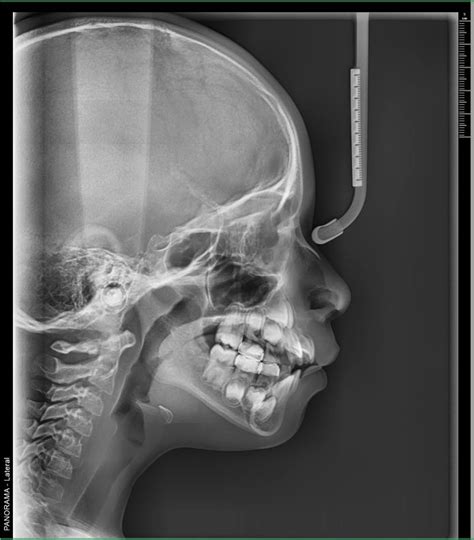

- Cefalometría o telerradiografía: Es la prueba tradicional para efectuar tratamientos de ortodoncia. Permite conocer el estado de los huesos del cráneo y de la cabeza en general: también de la boca. No obstante, no es muy utilizada en Odontonlogía. Telerradiografía lateral de cráneo: nos permite realizar mediciones y ángulos cefalométricos que nos son útiles para conocer el patrón de crecimiento del paciente joven y el patrón facial en jóvenes y adultos. Es la prueba tradicional para efectuar tratamientos de ortodoncia. Este tipo de radiografía dental se usa primordialmente antes de comenzar con un tratamiento de ortodoncia, ya que permite hacer un seguimiento del crecimiento y la relación intermaxilar. Se realiza una proyección del perfil de los huesos del cráneo, que nos permite detectar anomalías morfológicas, de colocación y/o de crecimiento de los dientes y así planificar el tratamiento de ortodoncia.

Ejemplo de radiografías extraorales.